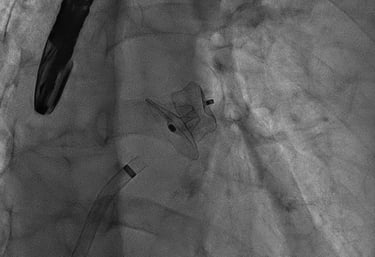

ANGIOPLASTICA

Angioplastica coronarica e lo stent

Si tratta del piu' comune trattamento attualmente utilizzato per curare l'aterosclerosi coronarica. E' una metodica che si avvale di molteplici strumenti appositamente ideati e realizzati e puo' essere effettuata subito dopo la coronarografia, utilizzando la stessa via di accesso arterioso. Solitamente, il paziente sottoposto ad angioplastica coronarica programmata puo' essere dimesso il giorno successivo alla procedura. Lo stent coronarico e' un dispositivo di grandezza millimetrica, in lega metallica biocompatibile (quindi senza fenomeni di rigetto), che viene utilizzato di solito dopo la dilatazione dell'arteria coronarica con il palloncino, per mantenere la pervietà della arteria.